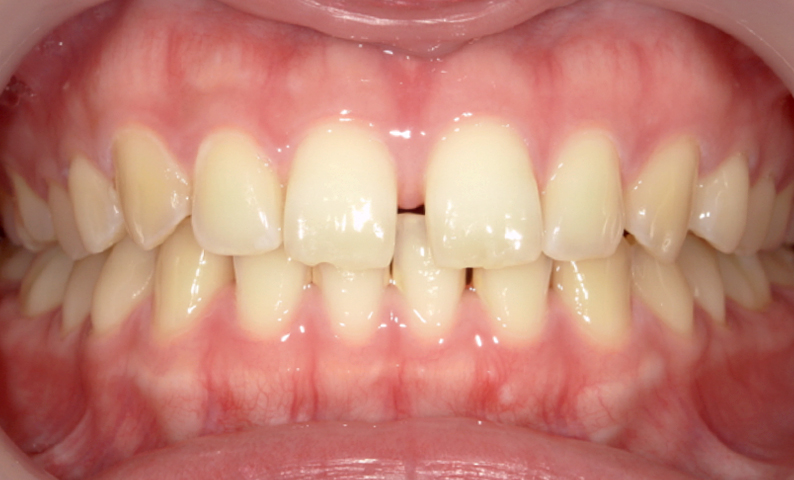

症例_003 前歯「すきっ歯」症例

治療期間:8ヶ月金額:48万円+税30代女性すきっ歯

| Before | After |

|---|---|

|